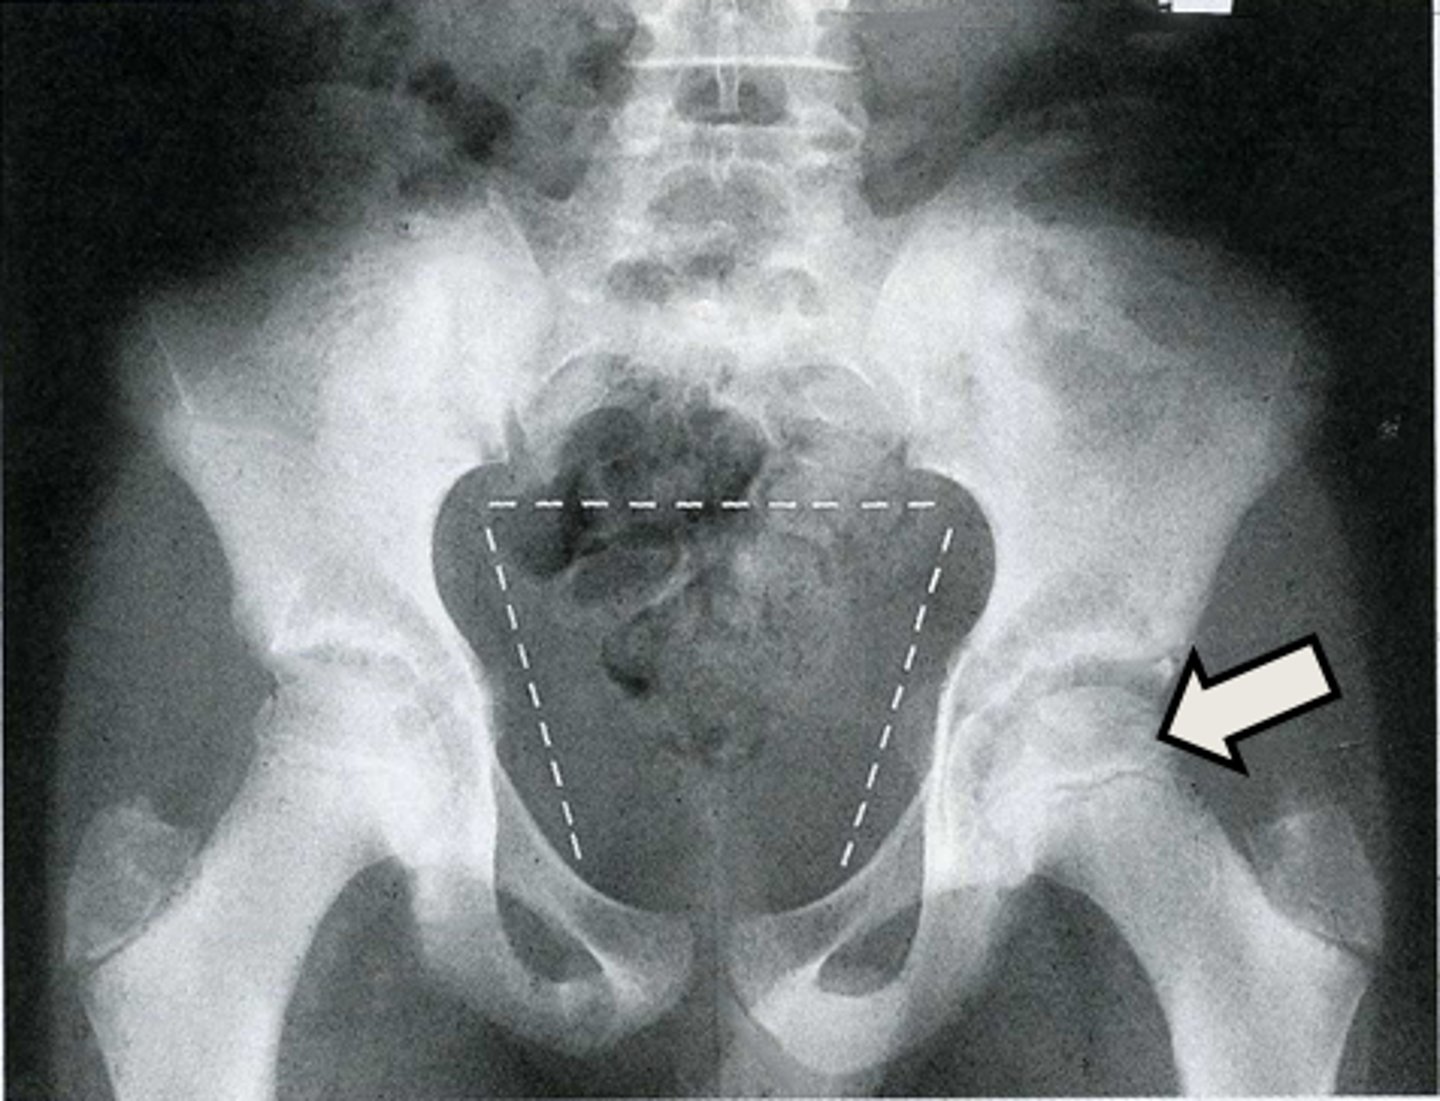

AP pelvis

What is the image?

L acetabulum

What is indicated in the image?

L anterior superior iliac spine (ASIS)

L ilium

L ischial tuberosity

L obturator foramen

L sacroiliac joint

L superior ramus of pubis

R acetabulum

R anterior superior iliac spine (ASIS)

R ilium

R ischial tuberosity

R obturator foramen

R sacroiliac joint

R superior ramus of pubis

Sacrum